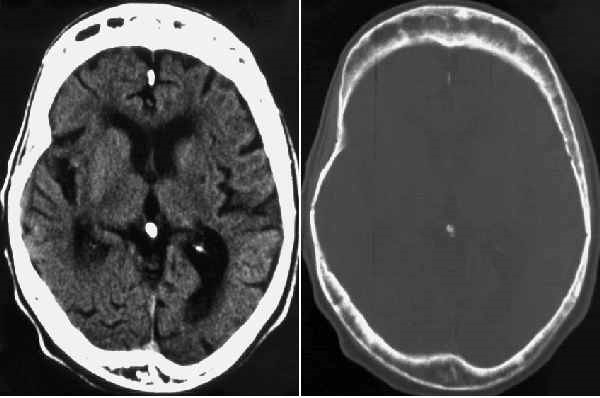

随着骨骼无序再生,它们可能改变形状。腿可能弯曲,脊柱可能异常弯曲,头骨可能增厚,甚至影响面部形状。